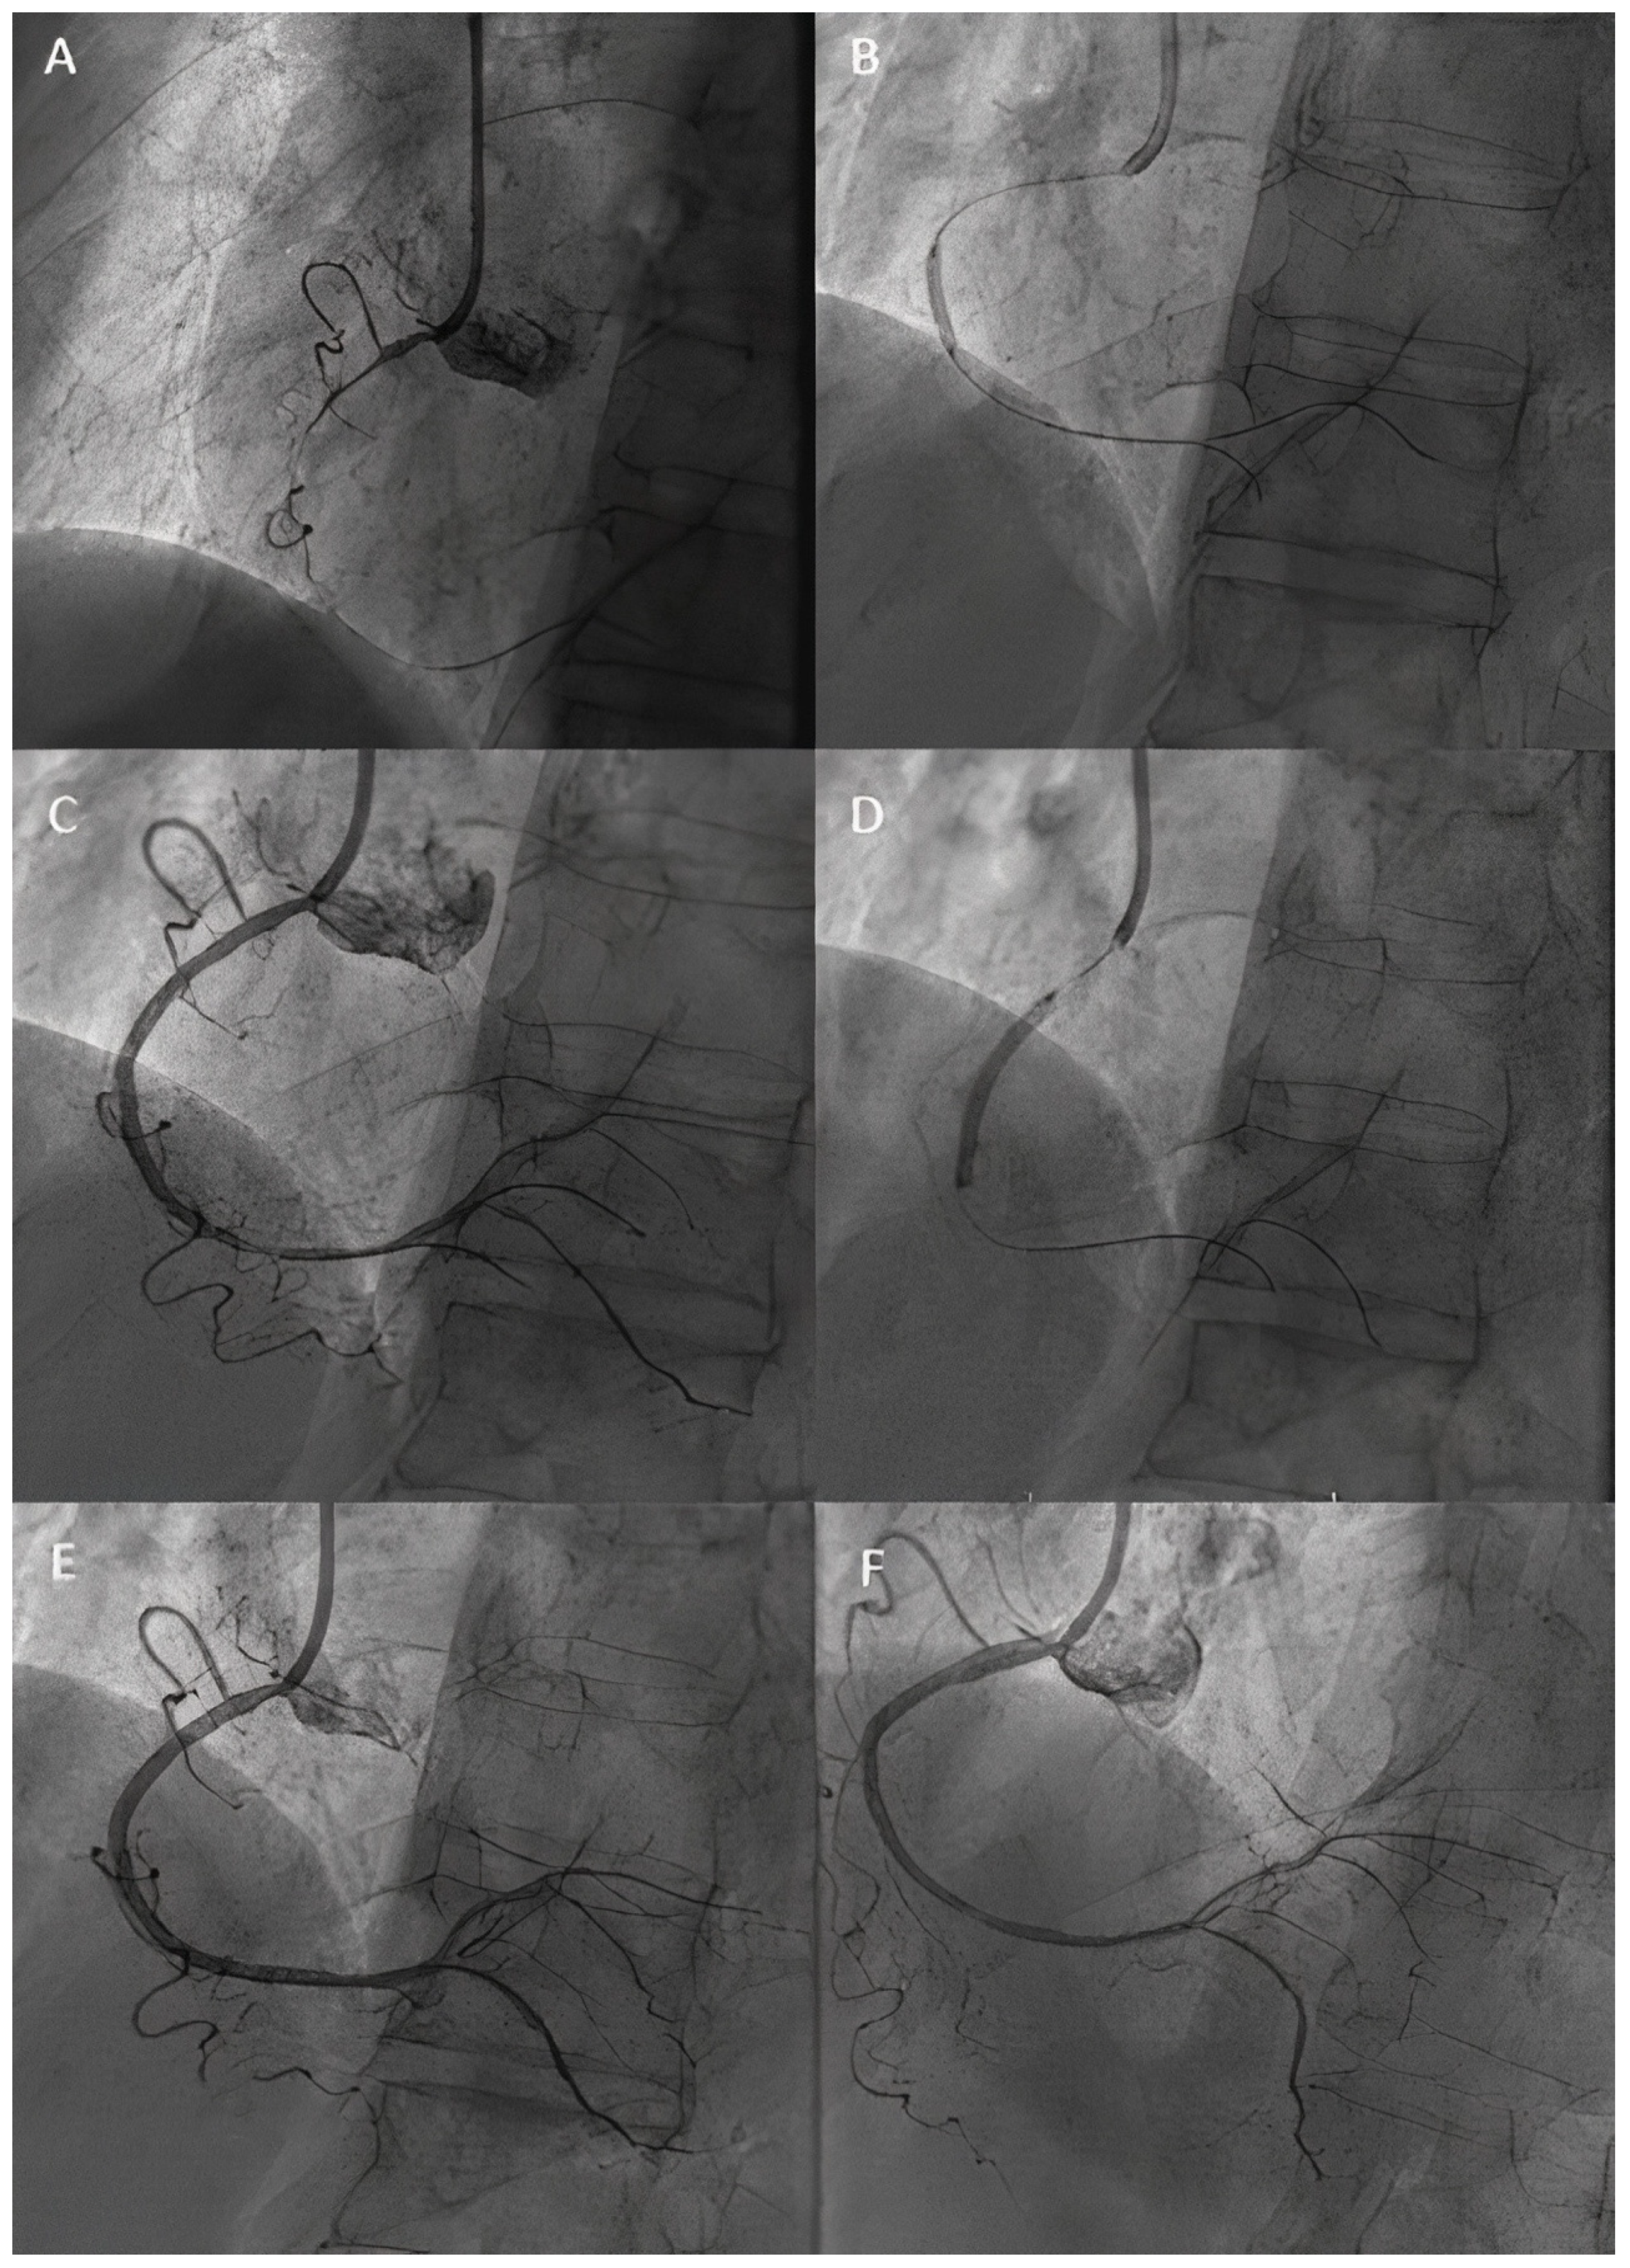

- Uskela, S.; Eranti, A.; Kärkkäinen, J.M.; Rissanen, T.T. Drug-coated balloon-only strategy for percutaneous coronary intervention of de novo left main coronary artery disease: The importance of proper lesion preparation. Front. Med. 2023, 17, 75–84. [Google Scholar] [CrossRef]

- Liu, H.; Zhao, Y.; Lu, Y.; Zhou, S.; Zhang, Y.; Zhao, J.; Yang, H.; Xing, J.; Feng, R.; Xue, X.; et al. The Drug Coated Balloon-Only Strategy for Treatment of de Novo Left Main Coronary Artery Bifurcation Lesion: Stentless Strategy. Clin. Appl. Thromb. Hemost. 2022, 28, 10760296221118489. [Google Scholar] [CrossRef]